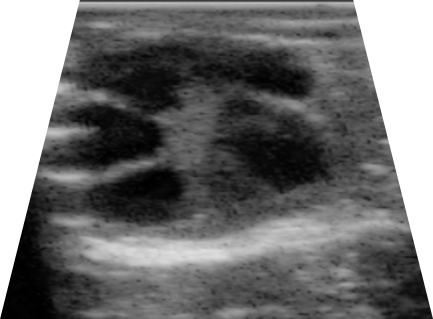

Características generales de la ultrasonografía de ovarios. Los pasos previos fueron de sujeción y preparación de llamas higienizando la zona perineal y su vulva, además del transductor puesto que la evaluación fue realizada por vía transvaginal con un equipo SonoStar SS8 (SonoStar Thecnologies, China) con un transductor microconvexo lineal endocavitario (V6S9 multifrecuencia: examen transvaginal) a 6.5 MHz en modo 2B para observar un lado para cada ovario (Figura 1) con la opción de freeze se paralizó las imágenes15-17para su almacenamiento y posterior evaluación, tal como se detalla a continuación:

Caracterización de la desviación folicular. Las evaluaciones fueron realizadas diariamente a partir del día de ablación folicular (día 0) durante las mañanas a cada uno de los animales, primero identificando a cada uno de los folículos como F1, F2, F3 y F4 según sea el caso, siendo para una solo FD el F1 como futuro folículo desviado9,20. Identificando a los folículos como estructuras redondeadas definidas y anecogénicas, las mediciones se hicieron por el interior de las paredes foliculares, tomando dos diámetros utilizando el promedio de estas como diámetro final de los folículos4,21.